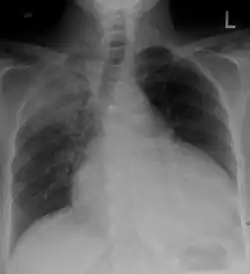

Chest x-ray: is non-specific and may not help identify a pericardial effusion but a very large, chronic effusion can present as "water-bottle sign" on an x-ray, which occurs when the cardiopericardial silhouette is enlarged and assumes the shape of a flask or water bottle.[2] Chest radiograph is also helpful in ruling out pneumothorax, pneumonia, and esophageal rupture.

Pericardial effusion due to malignancy. Note bulbous heart and primary lung cancer in right upper lobe.